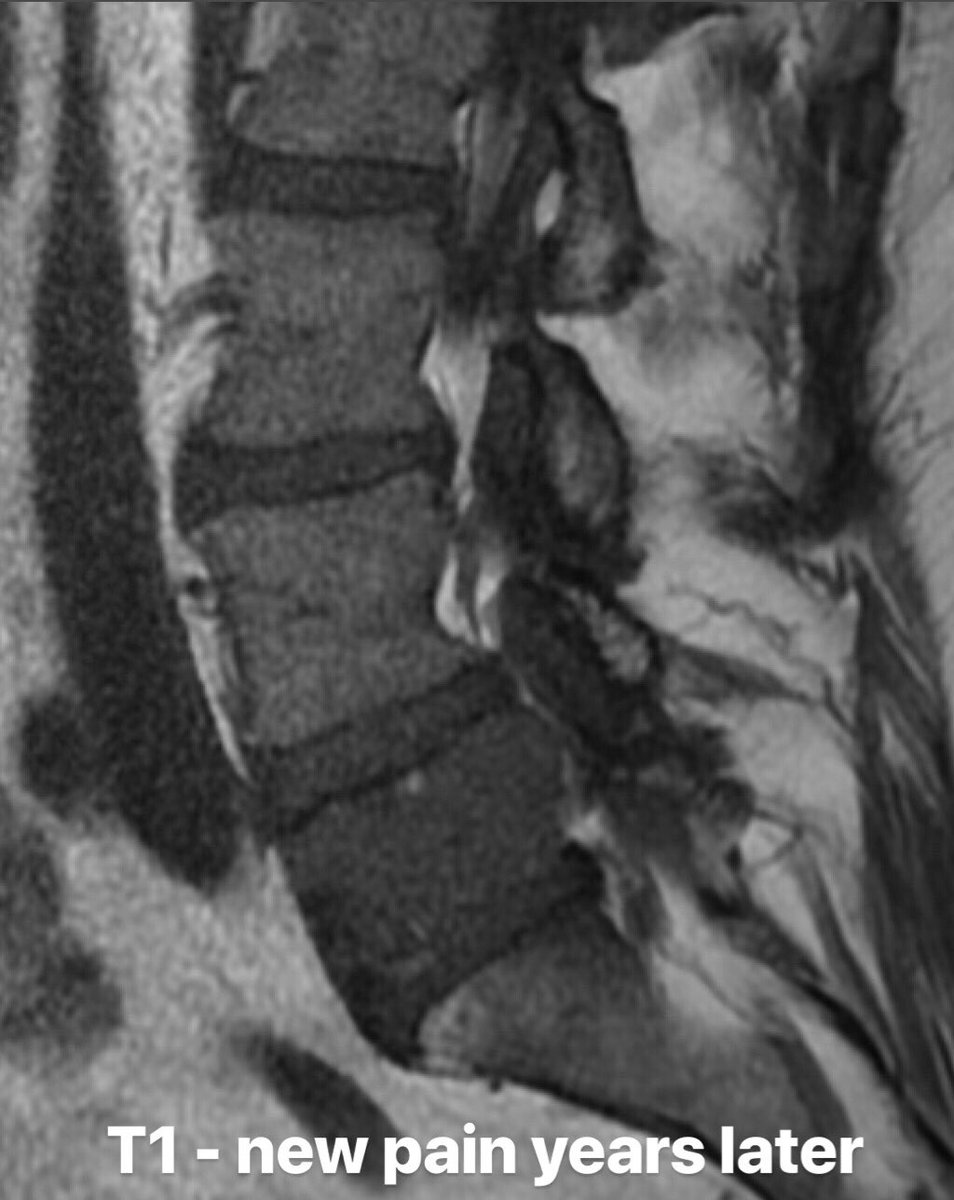

Importance of changing your

#ddx with evolving imaging findings: pt c/o new#LBP; had fat-filled L5 VB lesion years earlier (pic 1), now hypointense on T1 (pic 2). Bx confirmed plasmacytoma which had grown into prior benign hemangioma.#spine#neuro#UofUSpine#FOAMrad#SpineRad pic.twitter.com/lkDhiGTwlP